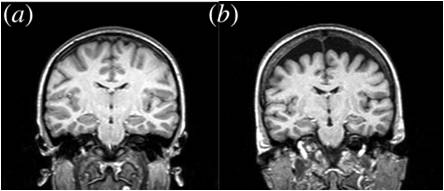

Selective Atrophy of Left Hemisphere and Frontal Lobe of the Brain in Old Men

Reading the abstract or introduction alone is enough to confirm what image (b) is telling us, massive erosion in the most recent

and advanced areas of our perceptual equipment, our new brain is literally withering away.

This is basically an unmodified selfie that exposes the underling and obvious cause of our current predicament.

Think about the emergence of dominator culture and the current hierarchical patriarchy of old men that have shaped our recent history and drive our society’s industrial-scale self-harm then read it again.

To be absolutely clear this is not just the ageing male brain, the condition originates during earliest development in the uterus and afflicts everyone one of us by degrees.

The associated psychological symptoms and perceptual limitations are variable and long precede the structural failure and withering of our neural system.

Those same psychological symptoms have left us nearly blind to the nature of the condition and dismissive or even hostile when confronted with its evidence.